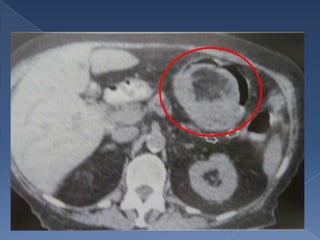

• 7.

Es dificil diferenciar entre maligno Imagen en y beningno manzana cuando miden mordida 1 cm o menos los polipos El tumor Coloscopia crece y enema no periluminal y determinan causando estadio estrechez